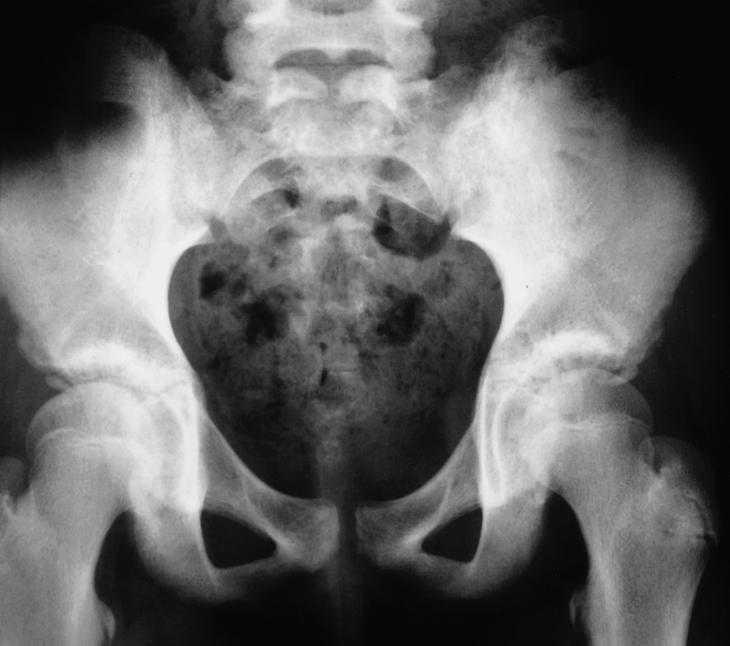

Se realizó analítica completa que incluyó hemograma, bioquímica con enzimas hepáticas, calcio, fósforo, fosfatasa alcalina, proteinograma, alfa-1-antitripsina, inmunoglobulinas y función renal, cuyos valores estuvieron dentro del rango de la normalidad. La velocidad de sedimentación globular (VSG) fue de 40 mm. La radiografía de tórax y la ecografía abdominal no evidenciaron alteraciones. En la radiografía de las sacroilíacas se observó una sacroilíaca izquierda con márgenes irregulares y mal definidos (fig. 1). En la gammagrafía con 99mTc se describió una lesión localizada en la sacroilíaca izquierda que deformaba y superaba esta articulación, con bordes abollonados hipercaptantes de forma moderada y áreas frías centrales. Se llevó a cabo una tomografía axial computarizada (TAC) de las sacroilíacas que puso de manifiesto alteraciones en la arquitectura trabecular del hueso ilíaco izquierdo con focos de lisis y esclerosis ósea adyacente a la articulación (fig. 2). En la resonancia magnética (RM) de las sacroilíacas se observaron cambios en la intensidad de la señal del componente medular de la pala ilíaca izquierda, con alternativa de hipo e hiperintensidad, y asimetría tenue de partes blandas con leve aumento de volumen en las zonas próximas al hueso sugestivo de proceso infiltrativo tumoral (fig. 3). En la TAC torácica se describió una imagen nodular en el lóbulo inferior izquierdo en los segmentos posteriores compatible con metástasis pulmonar. La biopsia de médula ósea no mostró signos de infiltración neoplásica. Se realizó una biopsia de la lesión que evidenció un tumor indiferenciado de célula redonda pequeña, con afección de hueso, periostio y músculo esquelético así como la presencia de fibrosis y desmoplasia estromal notables, sin signos de diferenciación. Los marcadores CD45, PAS, proteína S-100 y desmina fueron negativos. Se observó también manifiesta positividad de membrana para el anticuerpo CD-99 (O13), vimentina + + + y ENS (enolasa neuronal) + /-. Este patrón fue compatible morfológica, histoquímica e inmunocitoquímicamente con tumor de Ewing.

Figura 3. Resonancia magnética (RM) de sacroilíacas (T2). Aparecen cambios en la intensidad de la señal del componente medular de la pala ilíaca izquierda con alternativa de hipo e hiperintensidad. Asimetría tenue de partes blandas con leve aumento de volumen en las zonas próximas al hueso.